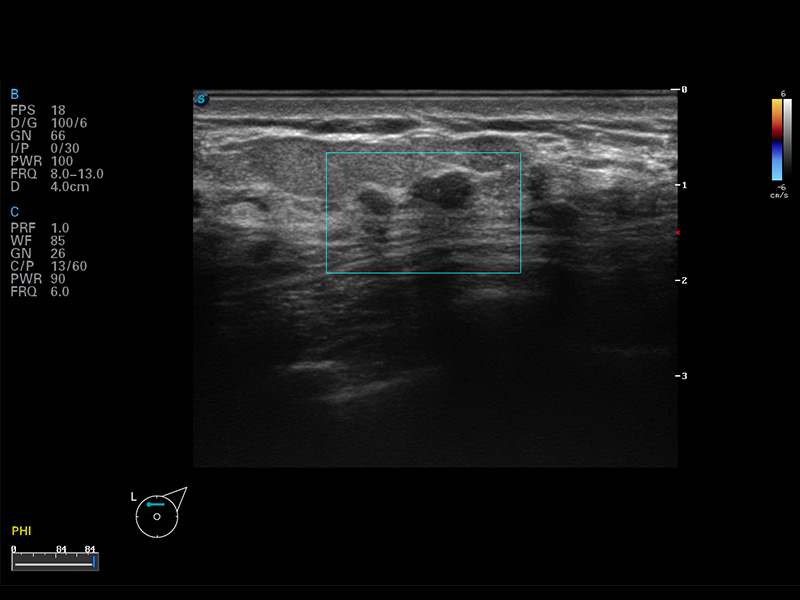

S8 EXP便携式彩色多普勒超声诊断仪是竞技宝(JJB)官方网站研发的高端全身应用型便携彩超。高通道的VIS平台融合可视化(Visual)、智能化(Intelligent)和人性化(Smart)的特点,配以竞技宝(JJB)官方网站自主研发生产的探头大家族,使您能够快速、准确的获得病人信息,提高工作效率的同时减轻疲劳。

μ-Scan微米成像